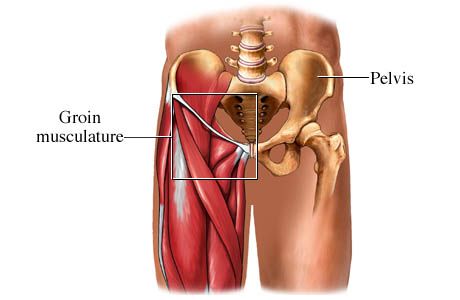

کف پا از پنج استخوان به شکل مداد تشکیل شده است که درست پشت انگشتان پا قرار دارند. این استخوانها به ترتیب در کنار یکدیگر قرار گرفته و در جلو با استخوانهای انگشتان پا و در عقب با استخوانهای زیر مچ پا مفصل میشوند. در بعضی فعالیتها مانند راه رفتن یا چرخاندن مچ پا، به این استخوانها نیروهای زیادی وارد میشود.

هنگامی که این نیروها از حد تحمل استخوان فراتر میروند، شکستگی ایجاد میشود. در بین استخوانهای متاتارس (استخوانهای پشتی پا)، استخوان پنجم بیشتر از بقیه به شکستگی مبتلا میشود و سپس شکستگی در استخوانهای متاتارس اول و دوم رایجتر از سوم و چهارم است. بسیاری از شکستگیهای استخوان متاتارس همراه با شکستگیها یا پیچ خوردگیهای مچ پا و اندام تحتانی همراه میباشد. شکستگیهای استخوان متاتارس از لحاظ موقعیت، شدت و ویژگیهای دیگر با یکدیگر تفاوت دارند.